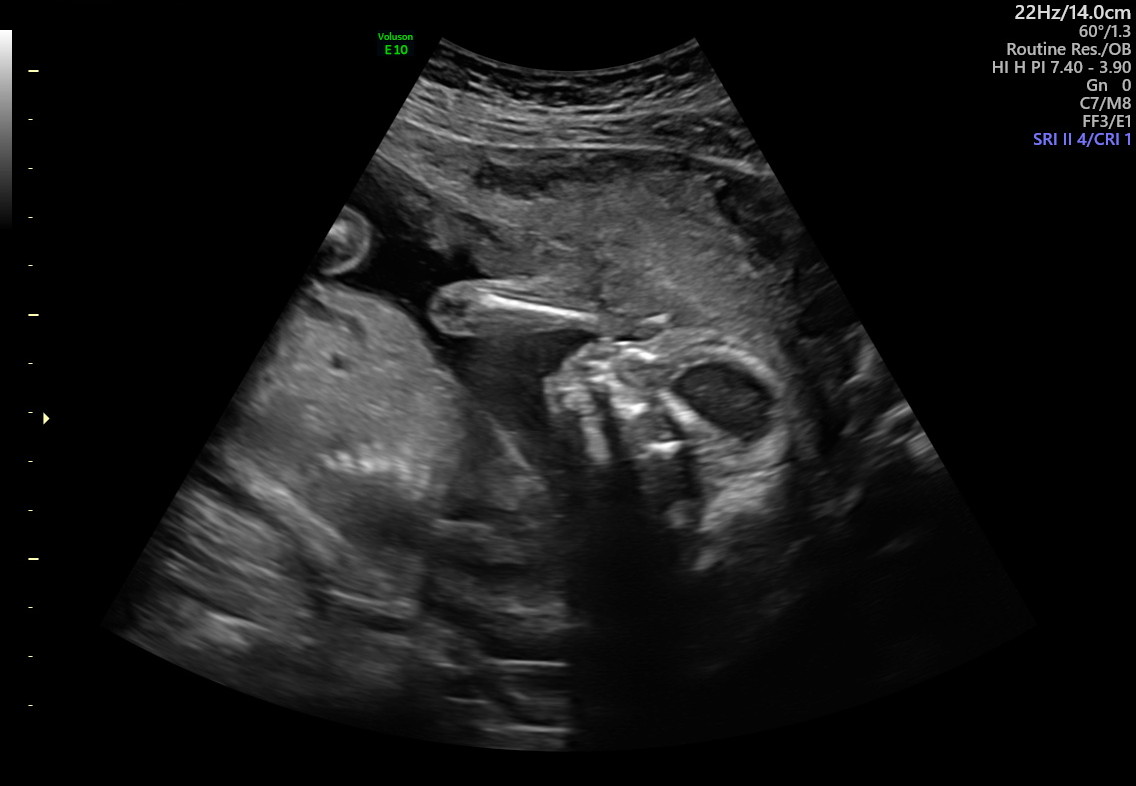

I’m currently pregnant with my second son. It’s strange to be pregnant in the middle of this massive debate. I feel my baby-to-be kick and move. He dances on my bladder and makes sleeping difficult, yet I love him beyond reason. The thought of losing him now makes my body clench and heart rate soar. Even so, if there was a choice now between my unborn son and my living toddler, it wouldn’t be a question. My toddler is here, alive, breathing, walking and talking. He is more a person to me than the wriggling mass and constant companion growing in my belly.

I also come from a place of knowing that my boys are healthy. My toddler runs and babbles. He says, “moo” when we ask what cows say. He mimics my movements. In every way, he exudes vitality. My unborn son has already undergone extensive screenings to rule out the possibility of Down syndrome or physical abnormalities. So far, everything has been blissfully normal.